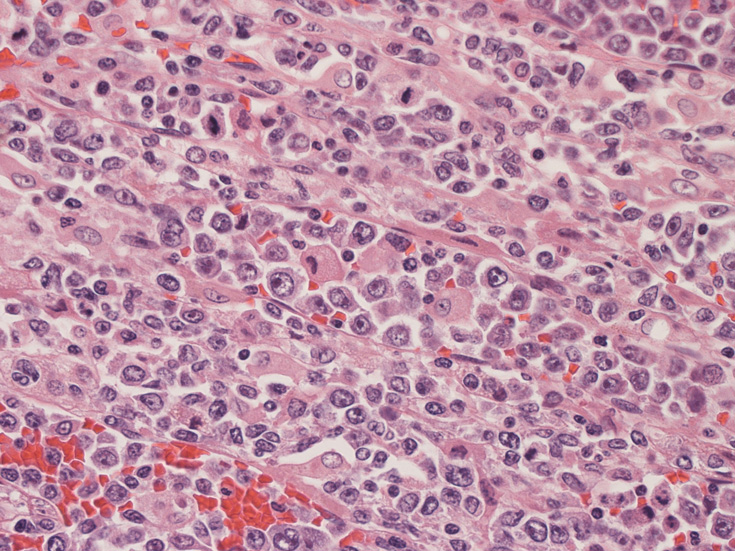

CD20陽性大型リンパ球の血管内増殖; 血管内増殖細胞はCD20陽性。

血管内異常リンパ球増殖症例であるが、細胞はCD20陰性, CD79a陰性, CD3陰性である。BCR, TCR遺伝子再構成も認められなかった。(細胞量の関係もあるか?). EBER-ISHは周囲小型リンパ球に陽性所見を認めたが腫瘍細胞はEBER(-)であった。

intravascular lymphomatosisはWHOの定義で intravascular large B- celllymphomatosisとされ、intravascular T-cell or NK cell lymphomaは異なる疾患群とされてる。本例ではB, T cellの証明ができなかった。異なるtypeのintravascular lymphomatosisの一例と考えられる. おそらくNK cell type IVL.

血管腔内に選択的に悪性リンパ腫細胞が増殖することを特徴とする節外性large B-cell lymphomaのまれなタイプ。WHOの定義ではBリンパ球の腫瘍であること, 血管内に腫瘍細胞が限局していることを診断の要件としている。歴史的には血管内皮の腫瘍性増殖とされneoplastic angioendotheliomatosisという用語が使用されてきたが, 1985年Moriらが免疫組織学的手法により増殖細胞がリンパ球あることを明らかにした*1